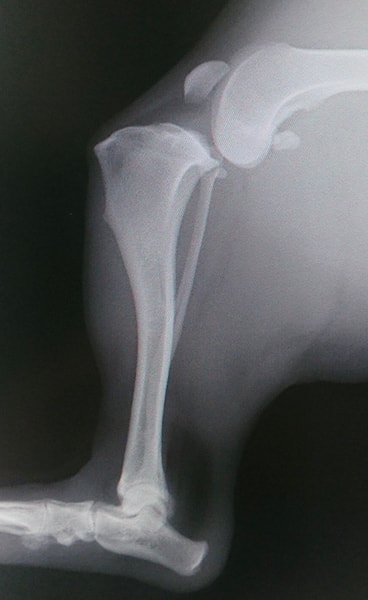

前十字靱帯断裂症例(2025/02/06)

HPの外科の前十字靱帯断裂のページに、犬のTPLO(脛骨高平部水平化骨切り術)手術を行った症例を追加致しました。大腿骨と脛骨を繋ぐ靱帯の一つである前十字靱帯が断裂すると、膝の関節が不安定となり関節炎が進行します。また膝関節内のクッションの役割を果たしている半月板にもダメージが加わり、痛みを生じて正常な歩行が出来なくなります。治療法としては術後の機能回復の早さから、近年ではTPLO法(脛骨の一部を円形に切り、角度を調整し膝関節を安定化させる手術)が多く選択されています。前十字靭帯断裂は中高齢犬によく見られる病気であり、膝蓋骨脱臼に併発することもあります。気になる症状がある場合はお早めにご相談下さい。

獣医師 臼井